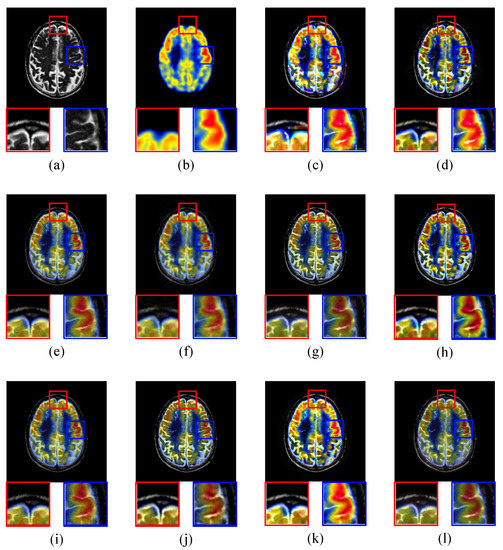

4.2.1. CT-MRI Image Fusion Comparative Experiments

4.2.2. MRI-PET Image Fusion Comparative Experiments

4.2.3. MRI-SPECT Image Fusion Comparative Experiments